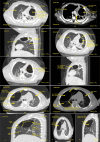

Figure 2

Figure 2. Case 1 (P1) (a) CECT scan of chest axial section in lung window (section 1) at the level of upper lobe showing a well-defined, thin-walled air containing cystic cavity lesion with surrounding lung parenchyma shows changes of passive collapse in left lung upper lobe. (b) CECT of section 1 in mediastinal window at level of upper lobe showing well-defined air-containing cavernous lesion with thin wall on CECT scan. (c) CECT of chest sagittal section in lung window showing air containing well-defined cystic lesion noted in left upper lobe with adjacent areas of collapse and left oblique fissure which separate left upper and lower lobe. (d) CECT of (section 1) in lung window at level of upper lobe showing a well-defined air-containing cavernous lesion in left upper lobe with upper lobar subsegmental bronchus appear in direct contact with cystic lesion and adjacent areas of passive collapse. (e) CECT of (section 1) showing well-defined air-containing cystic lesion in upper lobe of left lung measuring approximately 31 x 22 x 21 mm suggests CPAM (Type I) more likely. (f) CECT of chest sagittal section showing well-defined air-containing cystic lesion in upper lobe of left lung measuring approximately 31 x 22 x 21 mm suggests CPAM (Type I) more likely. Case 2 (P2) (g) HRCT scan of (section 1) at level of upper lobe showing a big, well-defined, oval, thin-walled, air-containing cystic cavity lesion in anterior segment of right upper lobe. There is thin oblique internal septation noted in antero-inferior portion of cavity. (h) HRCT scan of (section 1) in mediastinal window at level of upper lobe showing a big, well-defined, oval, thin walled, air containing cystic cavity lesion in anterior segment of right upper lobe. Apical segmental bronchus abuts medial wall of cystic lesion. (i) HRCT scan of chest sagittal section in lung window at right lung showing a big, well-defined, oval, thin-walled, air-containing cystic cavity lesion in anterior segment of right upper lobe. There is thin oblique internal septation noted in antero-inferior portion of cavity. The cystic lesion also abuts posteriorly to oblique fissure and inferiorly to horizontal fissure. (j & k) HRCT scan of chest axial and sagittal sections showing big, well-defined, oval, thin-walled, air-containing cystic lesion in anterior segment of right upper lobe measuring approximately 52.5 x 36.6 x 41.7 mm (AP X TX X SI) suggests congenital pulmonary airway malformation (Type I) more likely.

CECT - Contrast-enhanced computed tomography; HRCT - High-resolution computed tomography; CPAM - Congenital pulmonary airway malformation; AP - Antero-posterior; TX - Transverse; SI - Supero-inferior; P - Patient Image Credit: Dr. Dharmendra B. Parmar